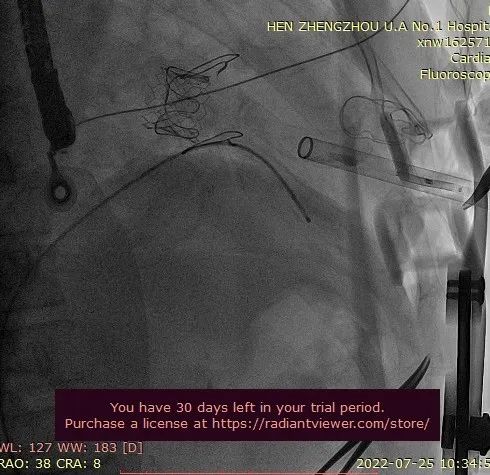

瓣膜释放过程

瓣膜释放后显示人工瓣膜位置良好、微量瓣周漏,跨二尖瓣平均压差为5mmHg,顺利完成手术。